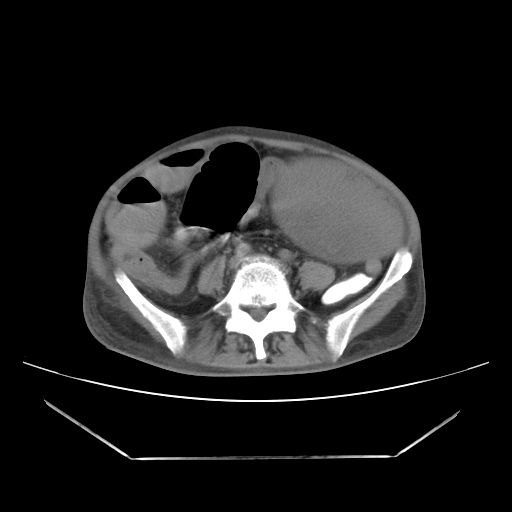

A 50 years old man with